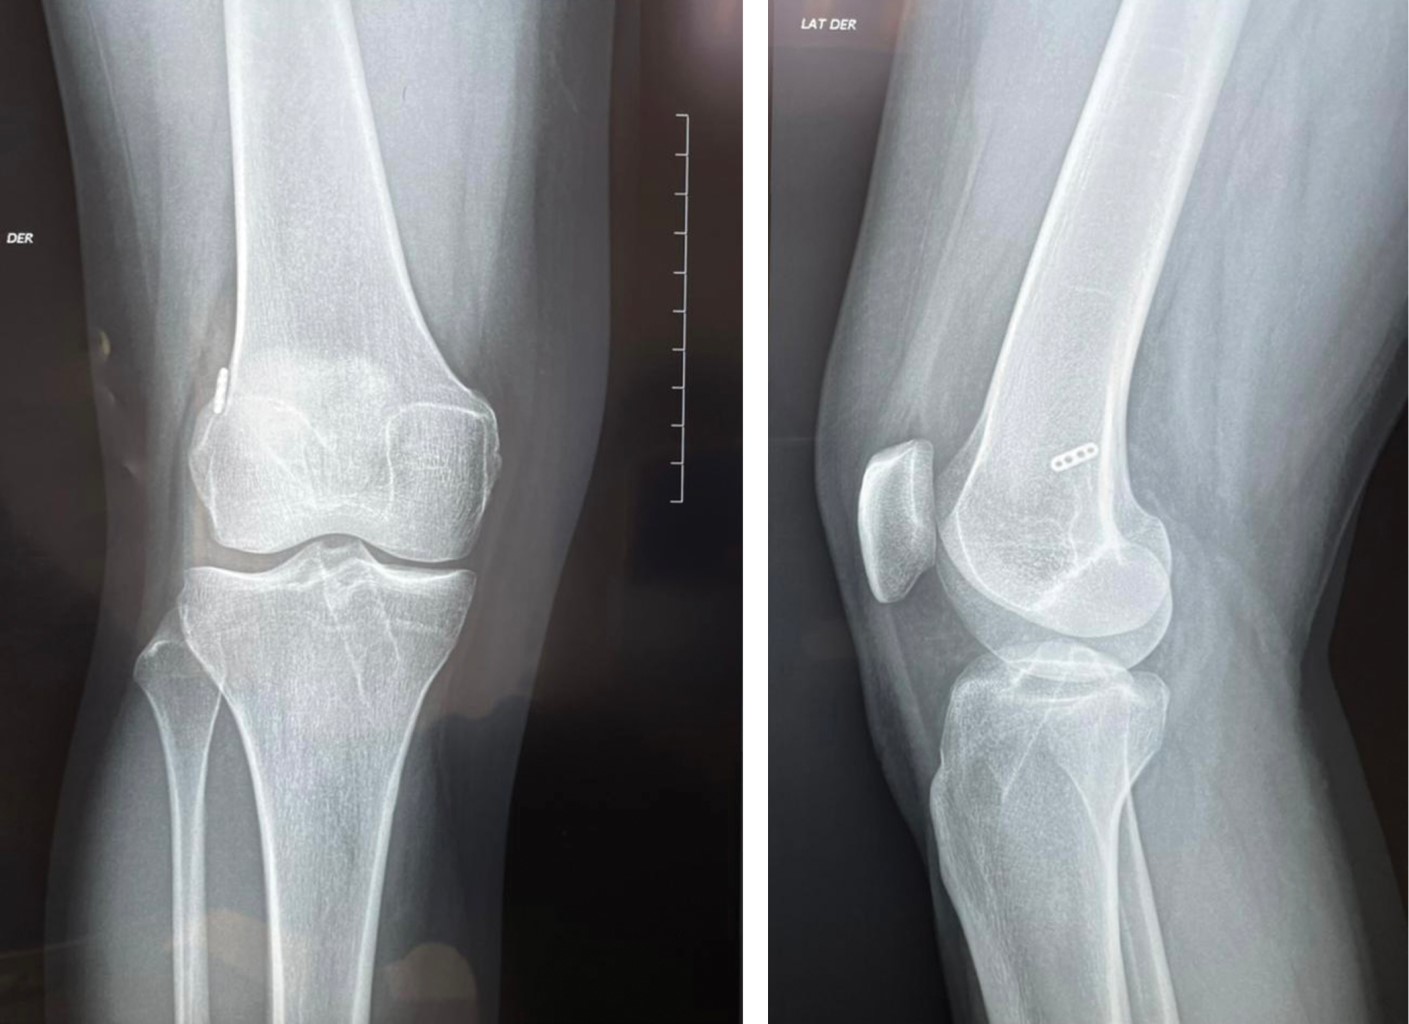

Anteromedial. Previa realización de túneles y selección de tamaño de Endobutton se pasa clavo guía por túnel femoral con una sutura de vycril del 0 o 00 para posteriormente recuperarla por el túnel tibial. Ya con la sutura se pasa el injerto con el sistema Endobutton (Figuras 1 y 2).

Se incluyeron 32 pacientes que se sometieron a reconstrucción del ligamento cruzado anterior con autoinjerto de isquiotibiales (Figuras 3 y 4), siendo 90.6% del sexo masculino, todos son de un nivel socioeconómico medio y tienen una baja participación deportiva en su vida diaria. La edad promedio del grupo estudiado fue de 27.7 ± 7.3, con un rango de 17 a 45 años. La talla promedio fue de 173.4 ± 6.9 cm. y el peso fue de 84.5 ± 16.4 kg, respecto al índice de masa corporal, fue de 28.15 ± 5.4 kg/m2, 21.9% de pacientes padece obesidad tipo II, 62.5% (n = 20) presentó lesión en su rodilla derecha, 53.1% (n = 17) se sometió a técnica quirúrgica con abordaje anteromedial y 46.9% (n = 15) abordaje transtibial. Sólo un paciente reportó tener una comorbilidad, hígado graso.

Figura 1

Figura 2

Figura 3

Figura 4